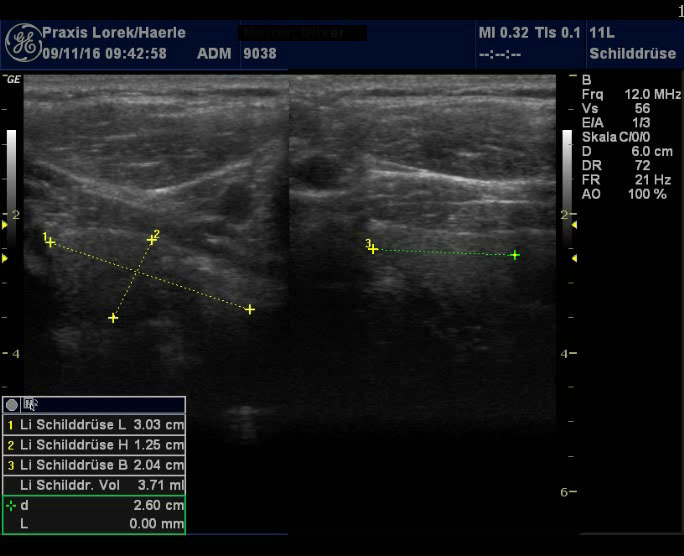

| Abb. 3 und 4: Tief liegendes

Schilddrüsenorgan bei einem 50-jährigen Mann mit deutlichen

Übergewicht, 162 cm und 103 kg. Die echoarmen subkutanen Schichten aus

Binde- und Fettgewebe sollten nicht als Schilddrüsengewebe fehlgedeutet

werden. Schilddrüse homogen, aber zu klein, TSH mit 2,25 im Normbereich,

zudem besteht ein Diabetes mellitus Typ IIb. |